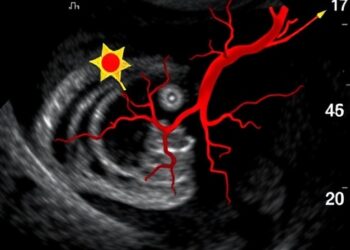

Ultrasound Reveals Arterial Thickness and Homocysteine in Diabetics

Recent advances in medical imaging technology, specifically high-resolution ultrasonography, have opened new avenues for understanding the cardiovascular complications associated with ...